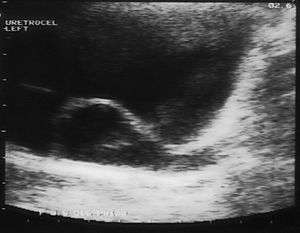

Ureterocele

A ureterocele is a congenital abnormality found in the ureter. In this condition the distal ureter balloons at its opening into the bladder, forming a sac-like pouch. It is most often associated with a duplicated collection system, where two ureters drain their respective kidney instead of one. Simple ureterocele, where the condition involves only a single ureter, represents only twenty percent of cases. Ureterocele affects one in 4,000 individuals, at least four-fifths of whom are female. Patients are frequently Caucasian.

Since the advent of the ultrasound, most ureteroceles are diagnosed prenatally. The pediatric and adult conditions are often found incidentally, i.e. through diagnostic imaging performed for unrelated reasons.